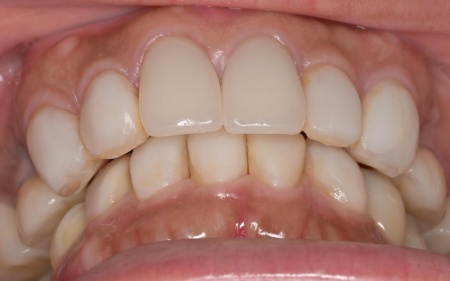

加えて、上前歯4本(左右側切歯・犬歯)と下前歯5本(左右中切歯・側切歯・右下犬歯)は、ダイレクトクラウンによる修復を行いました。

ダイレクトクラウンとは、レジン(樹脂)を用いて直接歯の形を作り上げていく治療方法です。

歯を削る量が少ない、色や形を細かく調整しながら仕上げられる、治療後は必要に応じて微調整がしやすいなどのメリットがあります。

最後に、見た目や噛み合わせに問題がないかを確認し、治療を終了しました。